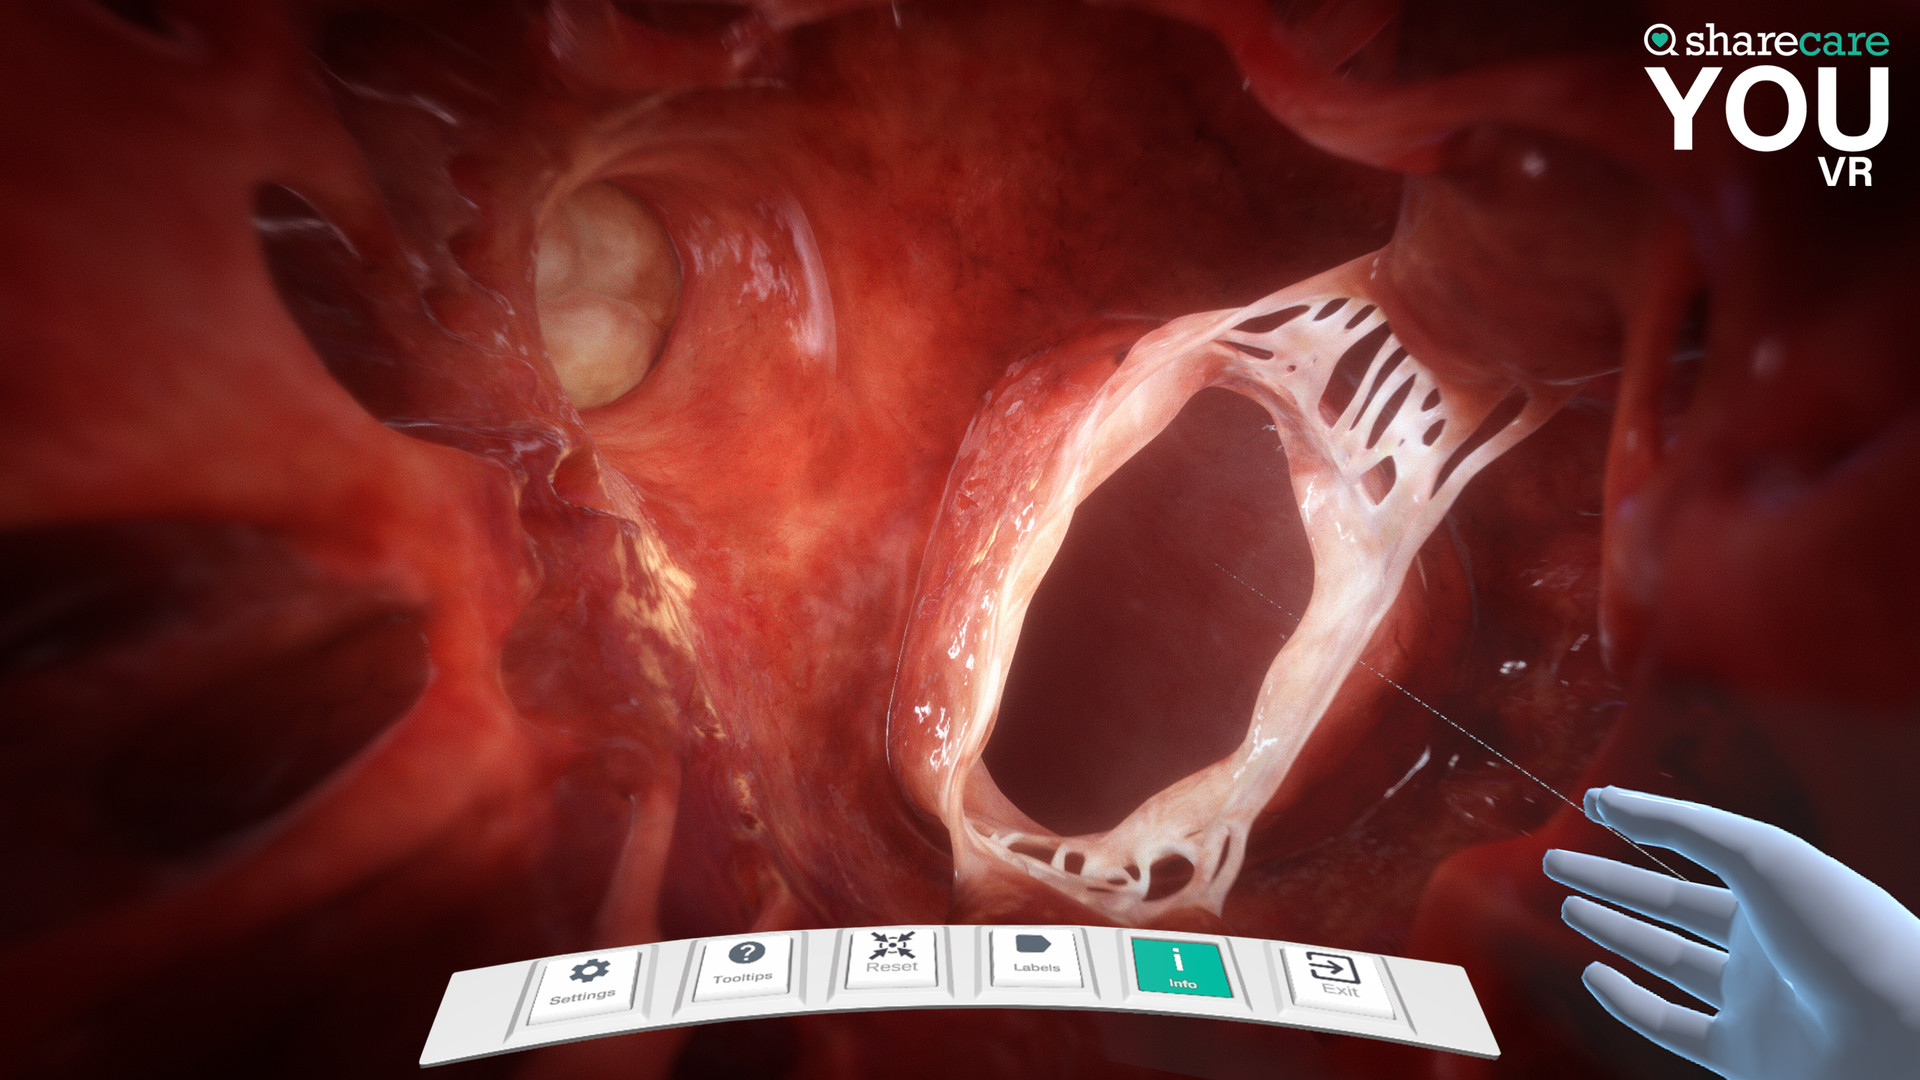

Sharecare YOU是一种完全身临其境的、逼真的人体模拟,让任何人都可以 360 度全方位探索其惊人的细节。

有兴趣了解特定器官吗?只需单击一个按钮,即可进入内部,想象其自然功能,并深入探索。想了解更多吗?查看沿途的许多标签和标签,以获得更多信息和洞察力。轻松定制您以更好地了解生理学和模拟疾病。您甚至可以将我们的头像个性化为虚拟的您——您的健康、您的状况。这真的是关于你的。

- 你的内容 – 一个包含 40 多个不同场景的扩展库供探索,包括解剖学、生理学、条件和治疗

- 具有独特交互式控件的完全更新的用户界面